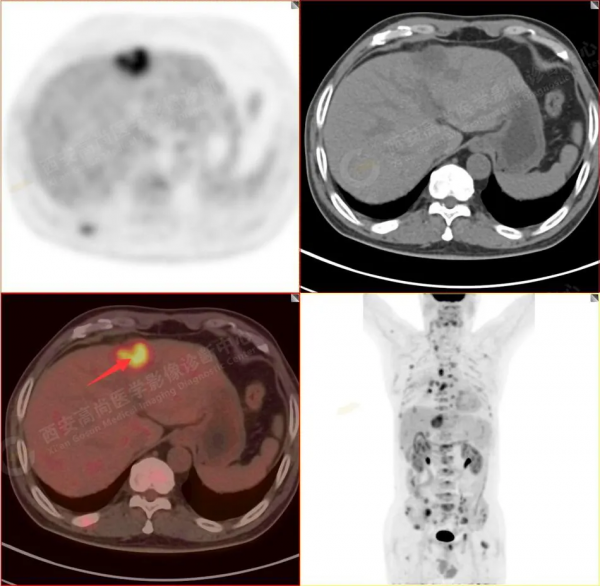

1.以下為肺內原發灶

1.右肺下葉後基底段軟組織結節(約1.5cm×1.2cm),與相鄰後胸膜分界不清,呈FDG代謝異常增高,結合病理,符合肺腺癌伴鄰近胸膜侵犯。

6.肝內小結節,考慮轉移可能性大,建議MR增強掃描。